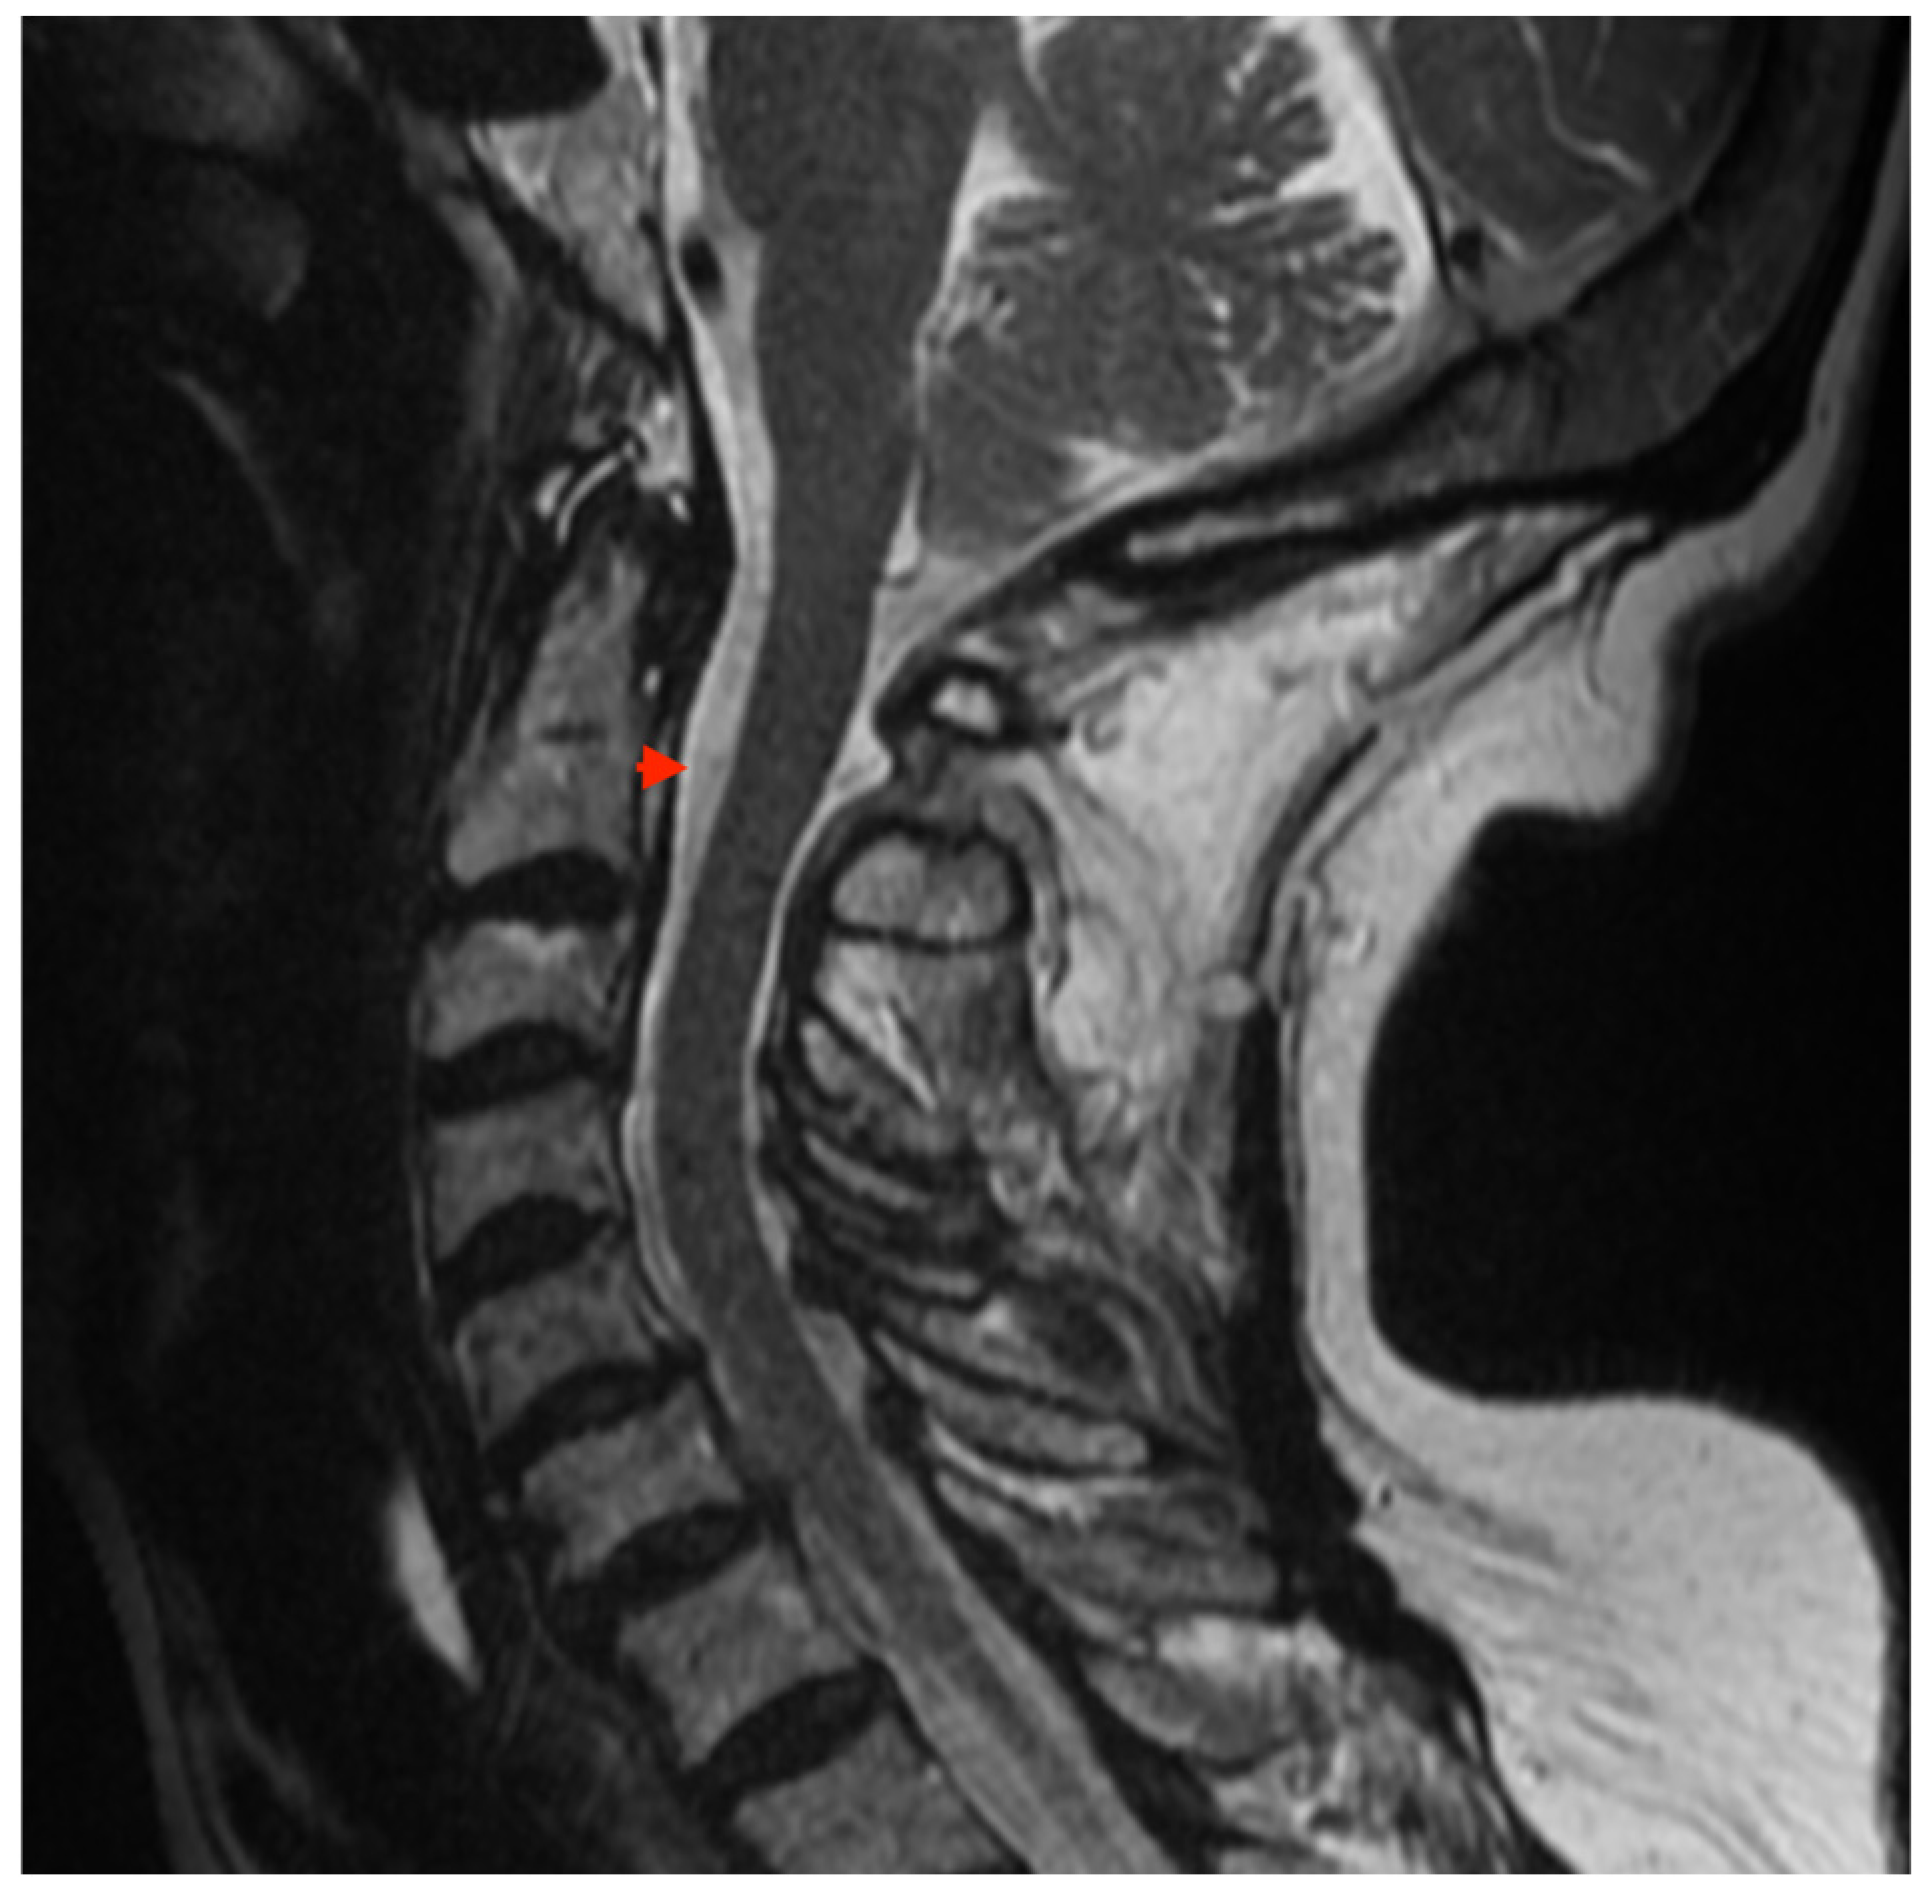

2. Case Presentation